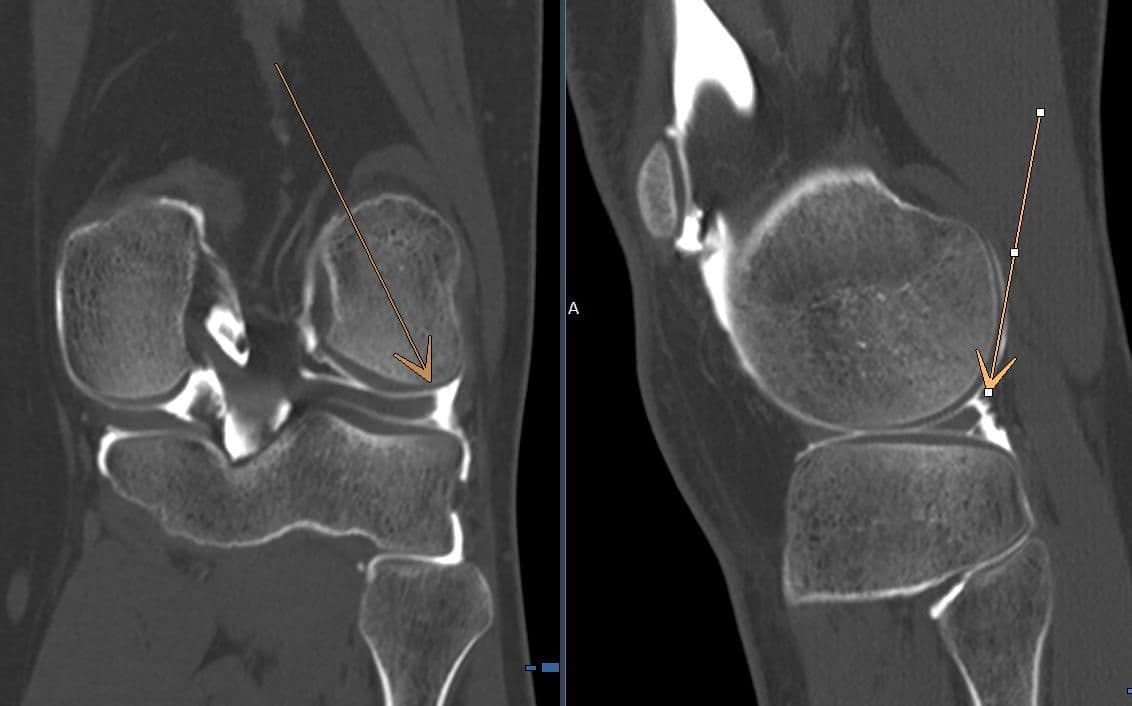

Apport de l'arthroscanner dans la recherche de fissure méniscale

genou

Apport de l'arthroscanner dans la recherche de fissure méniscale en complément de l'IRM

MRICT

Désinsertion capsulo méniscale latérale

Désinsertion capsulo méniscale latérale chez un jeune sportif de 17 ans.

CT